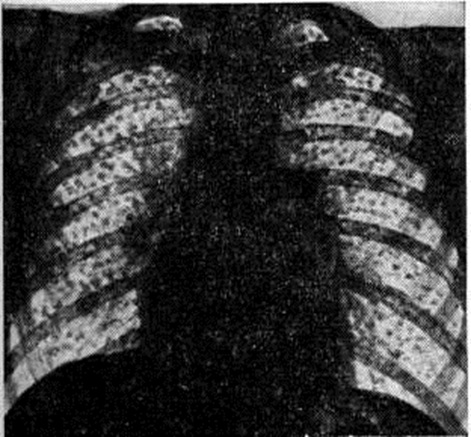

Узелковая форма Силикоз (рисунок 1) характеризуется наличием в лёгких мелких округлых чётко очерченных однотипных теней. В зависимости от фазы развития узелка (клеточная, фиброзная фаза, фаза гиалиноза или кальциноза) меняется интенсивность и гомогенность узелковых теней. По величине выделяют 3 типа узелков: до 1,5 миллиметров (р), от 1,5 до 3 миллиметров (q), от 3 до 10 миллиметров (г).

Рис. 1.

Обзорная рентгенограмма грудной клетки при узелковой форме силикоза (прямая проекция): множественные мелкие очаговые тени в обоих лёгочных полях.